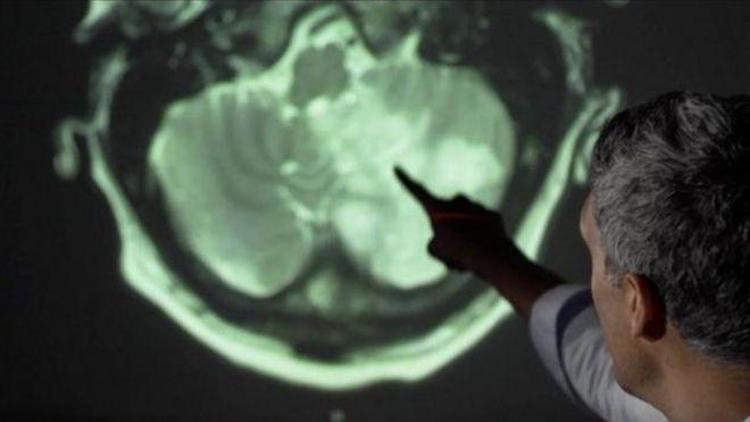

Covid-19 beyni nasıl etkiliyor?

Felç, deliryum, anksiyete, şaşkınlık... liste uzayıp gidiyor. Covid-19'un sadece bir solunum yolları hastalığı olduğunu düşünüyorsanız, tekrar düşünün.

Zaman geçtikçe, koronavirüsün çok sayıda nörolojik sorunu da tetikleyebileceği giderek netleşiyor.

125 hastada beyin sorunları

Lancet Psikiyatri dergisinde yayımlanan bir çalışmada, İngiltere'de hastanede yatan 125 ağır koronavirüs hastasında beyin problemleri tespit edildi.

Yaklaşık yarısı pıhtılaşma yüzünden felç geçirirken,diğerlerinde beyinde enflamasyon, psikoz ya da bunama benzeri semptomlar görüldü.

Araştırmayı yapan ekipten Liverpool Üniversitesi Profesörü Tom Solomon "Virüsün sadece akciğerlerde değil, beyinde de sorun yarattığı şu an açık. Bu kısmen beyine oksijen gitmemesinden. Ancak kanda pıhtılaşma, bağışıklık sisteminin tepkisi gibi başka faktörler de var gibi görünüyor. Ayrıca virüsün kendisinin de beyni enfekte edip etmediğini sorgulamalıyız" dedi.